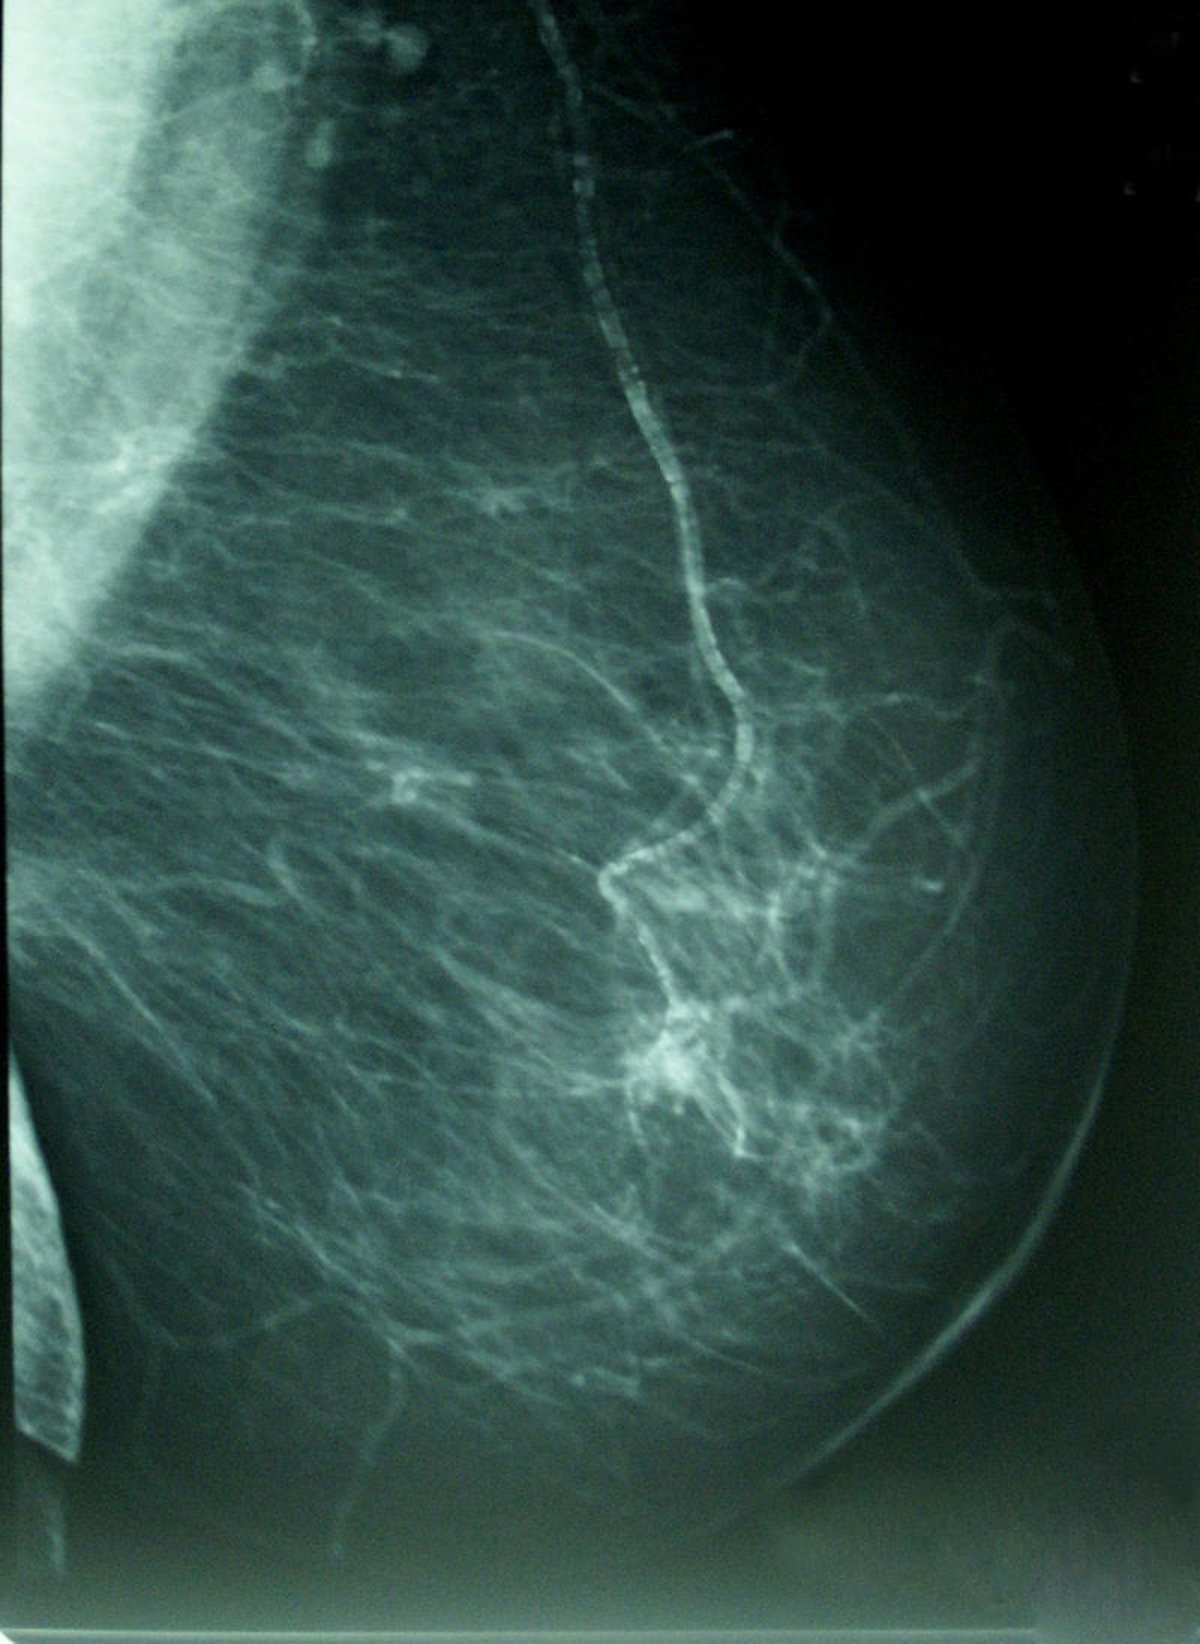

Cáncer De Mama, Densidad Mamográfica

WIKIPEDIA/A. AVENDAÑO

El Grupo Español de Investigación en Cáncer de Mama (GEICAM) lidera el primer estudio prospectivo encaminado a analizar qué cambios se registran en los receptores hormonales y de sobreexpresión del HER2 en pacientes desde que son operadas del tumor primario hasta que desarrollan la primera metástasis y la recaída se produce en una zona susceptible de hacer biopsia. En dicho estudio participa el Hospital Virgen de la Salud de Toledo junto a otros 34 hospitales del país.